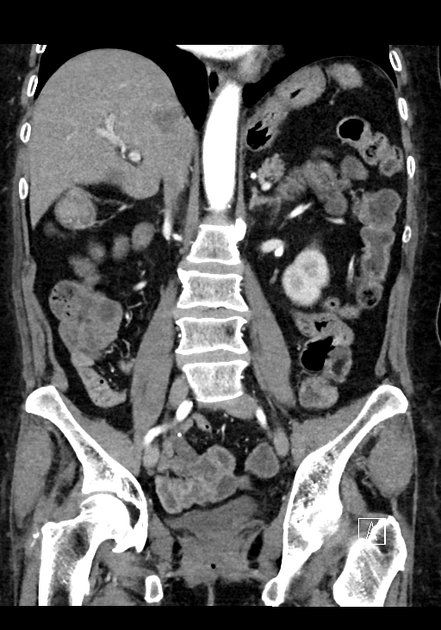

Coronal C+ delayed

Coronal C+ arterial phase